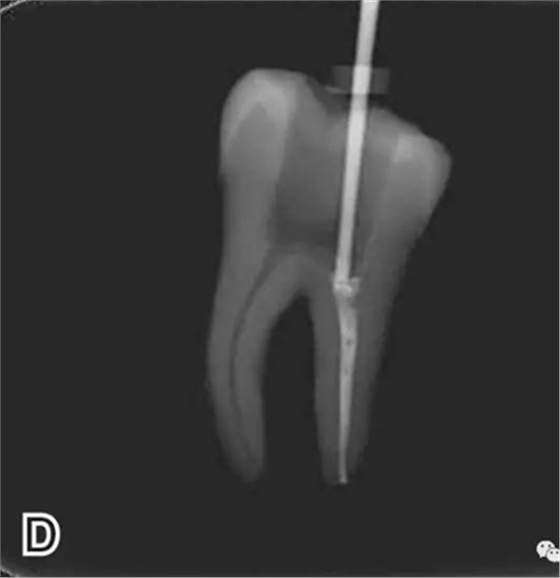

3、試尖

選擇非標(biāo)準(zhǔn)牙膠尖(如0.04、0.06 錐度牙膠尖)作為主尖,型號(hào)一般與根管預(yù)備最大號(hào)的器械型號(hào)一致,能到達(dá)距根尖0.5~1 mm 處,主尖尖段與根管壁緊密接觸。拍試尖X 線片進(jìn)行確認(rèn)(圖3)。

圖3 試尖,A.試主尖 B.拍試尖X片